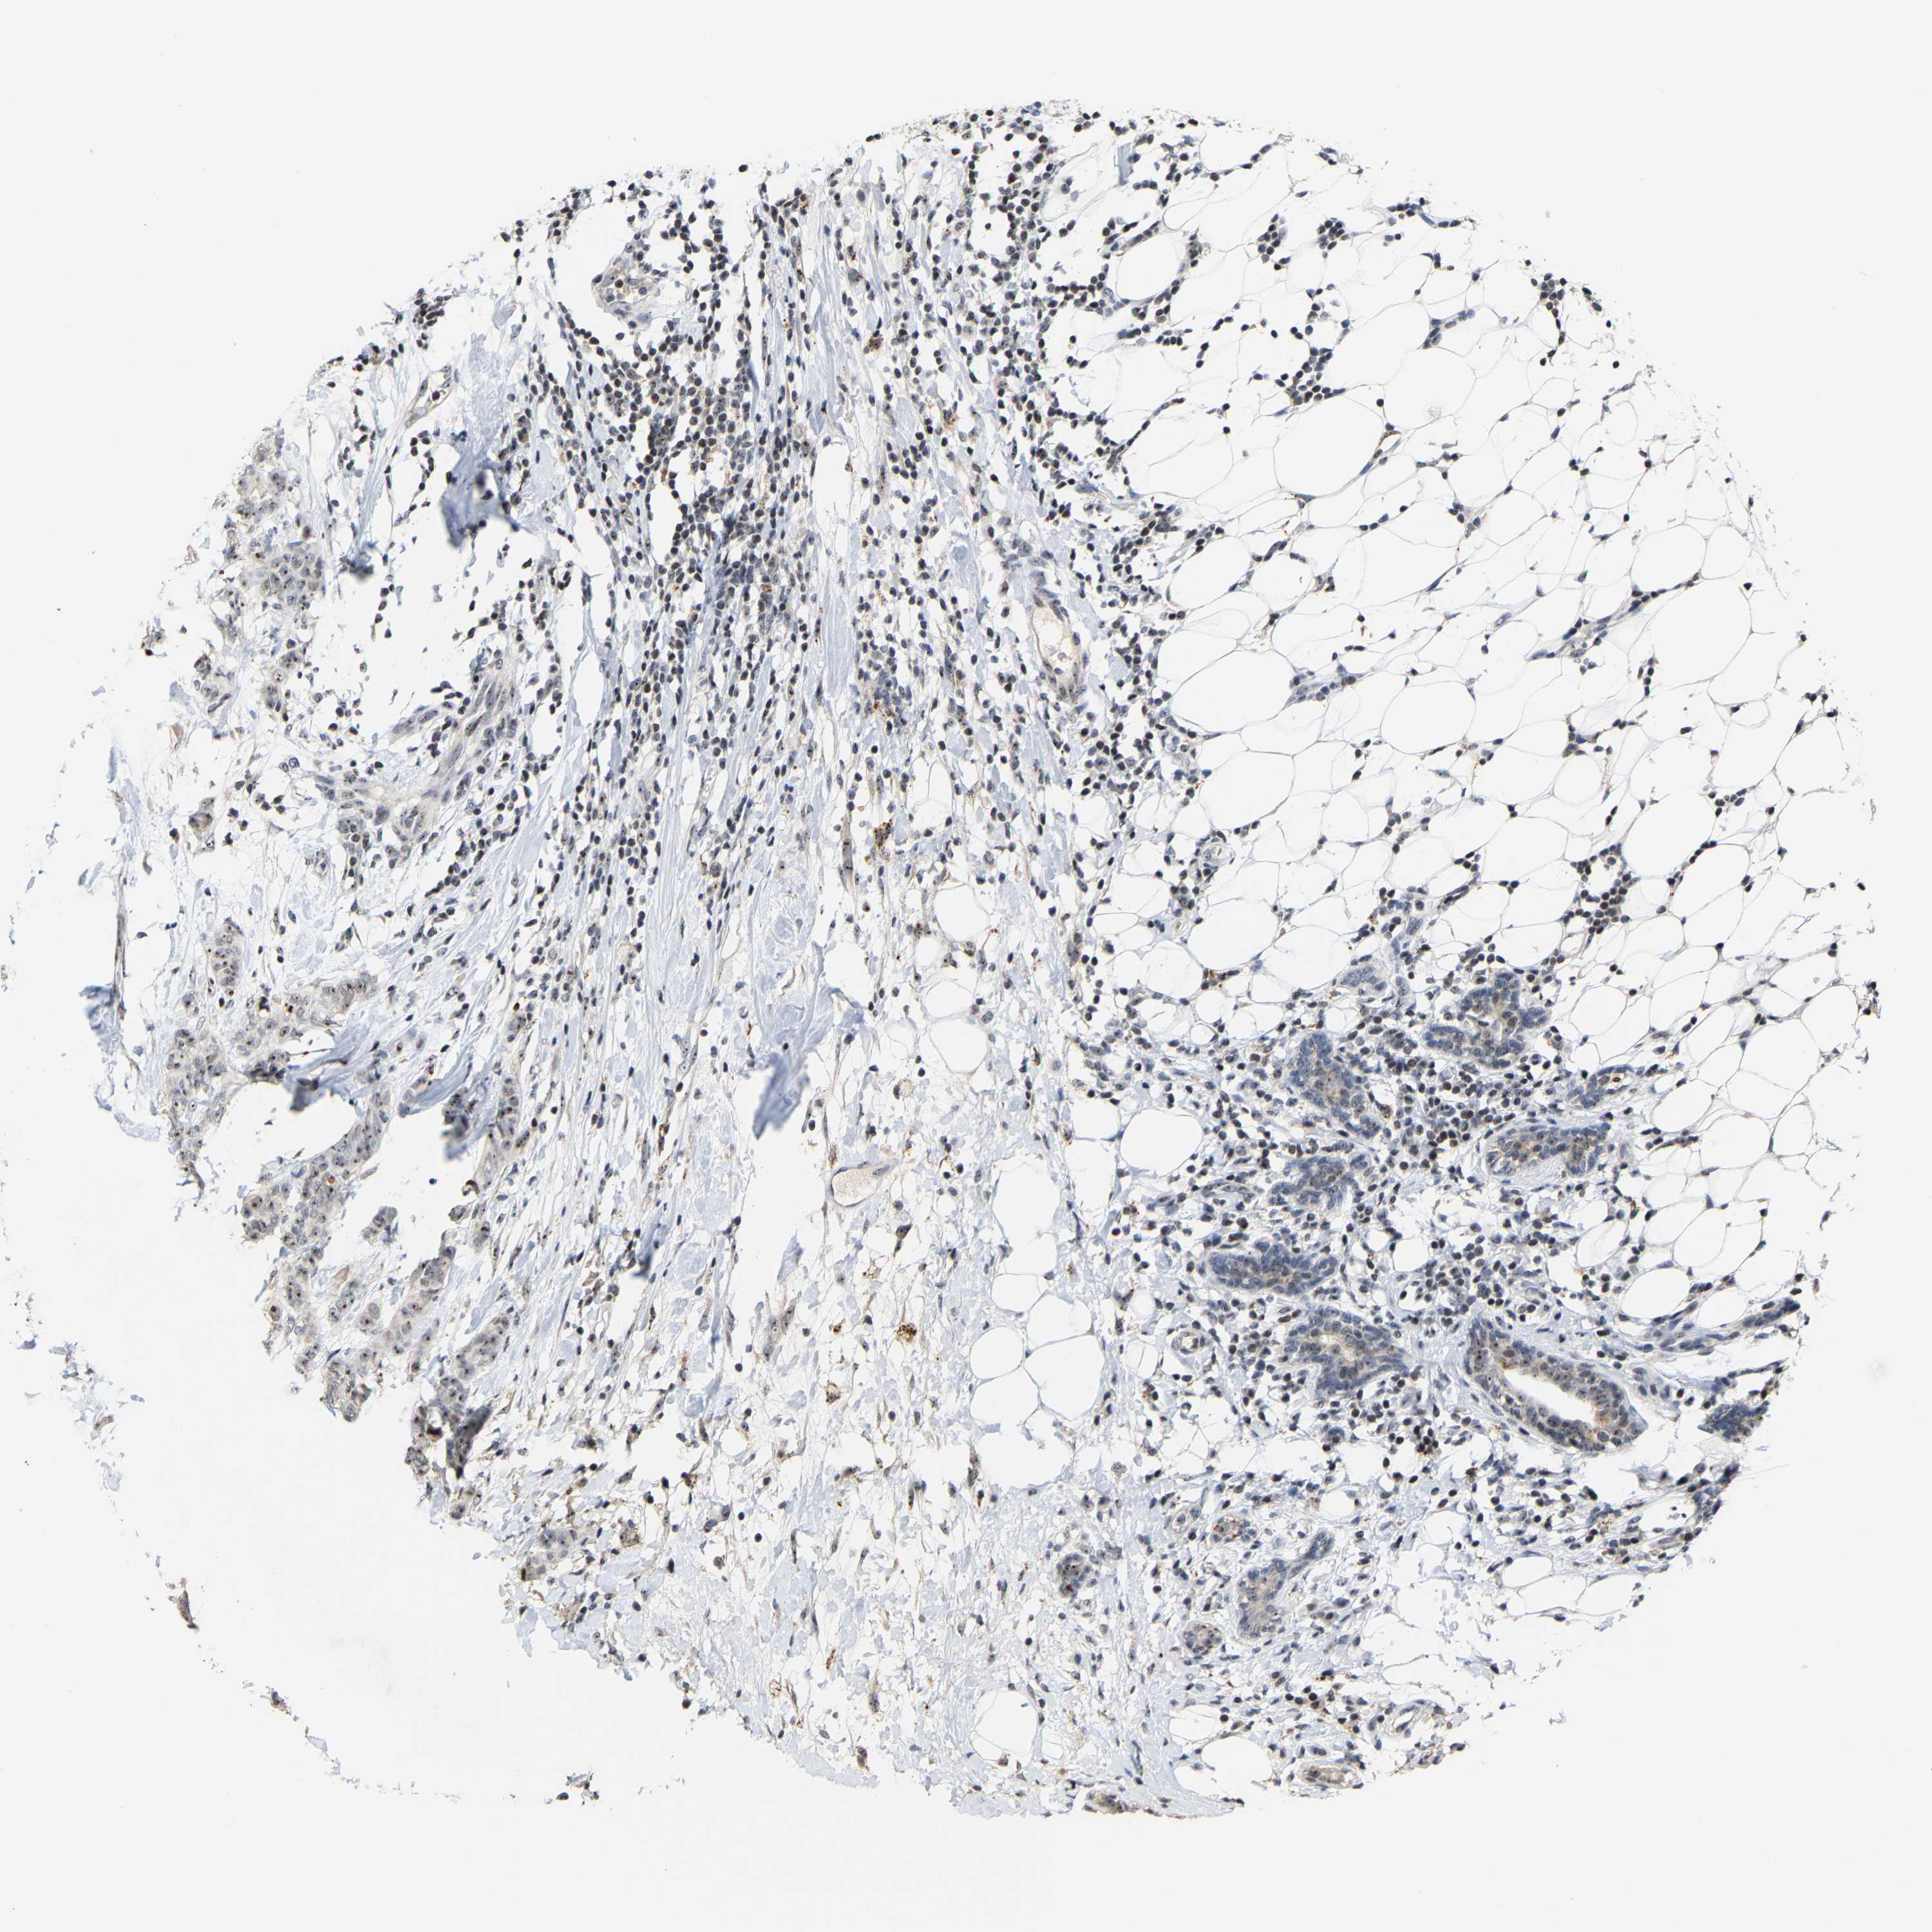

CANCER BREAST CANCER Show tissue menu

BRCA TCGA BRCA VALIDATION PROTEIN EXPRESSION